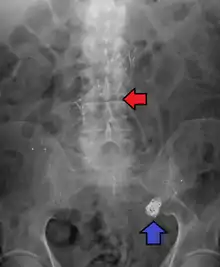

Illustration depicting location of abdominal aneurysm

Abdominal aortic aneurysm involves a regional dilation of the aorta and is diagnosed using ultrasonography, computed tomography, or magnetic resonance imaging. A segment of the aorta that is found to be greater than 50% larger than that of a healthy individual of the same sex and age is considered aneurysmal.[9] Abdominal aneurysms are usually asymptomatic but in rare cases can cause lower back pain or lower limb ischemia.